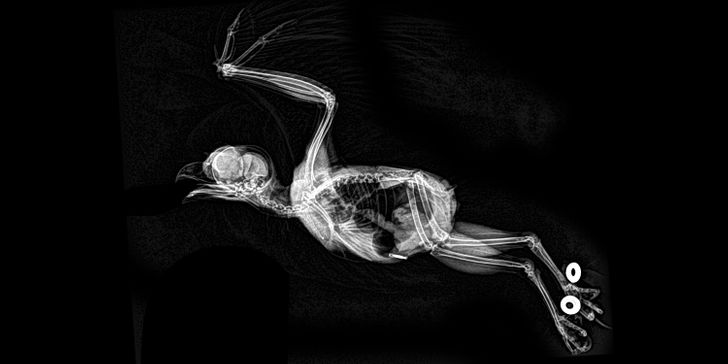

4. Pink flamingoes make elegant X-rays

Illustration de l'article : 14 X-ray images that reveal a hidden story

© 9w_lf9 / Reddit